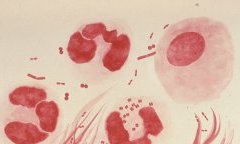

Epidémie

Le Gabon en alerte après la détection d’un premier cas de variole du singe (MPOX)

Le Gabon vient de confirmer son premier cas de variole du singe, ou MPOX, une infection virale qui, bien que rarement...